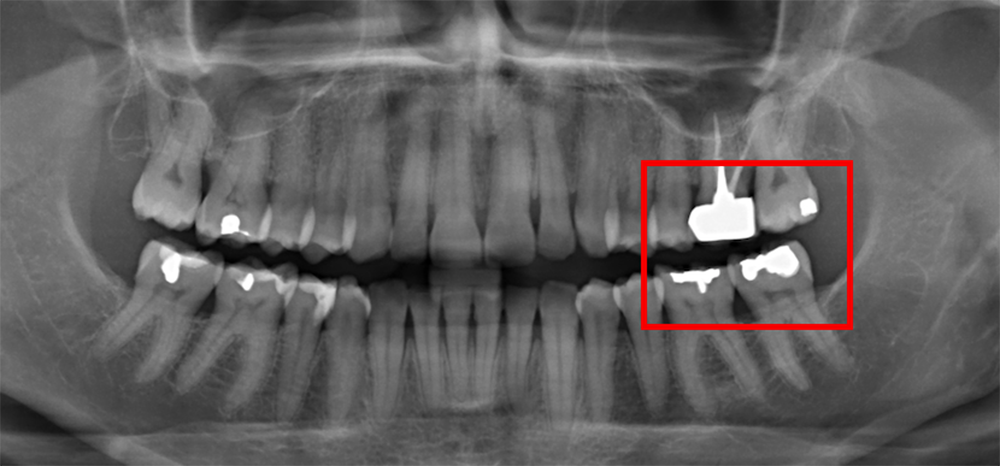

Radiographiquement, on observe une perte des cuspides et un aspect plan des faces occlusales (fig. 2a-b et 4a).

Cliniquement, les lésions d’abrasion sont caractérisées par des facettes lisses, une absence de convexité et des bords à angles vifs. La flexibilité du ligament alvéolo-dentaire va entrainer un frottement au niveau des points de contact, qui peuvent se transformer en surfaces de contact (fig. 2c-d, 3 et 4b-c).

- la nature du pilier sous-jacent. En effet, la perte de l’organe pulpaire va entrainer une perte de proprioception. Ainsi, une pression occlusale plus importante sera déclenchée avant d’atteindre le même seuil de détection qu’une dent pulpée. Pour un pilier implantaire, la proprioception sera également diminuée du fait de la perte supplémentaire des récepteurs desmodontaux [3].